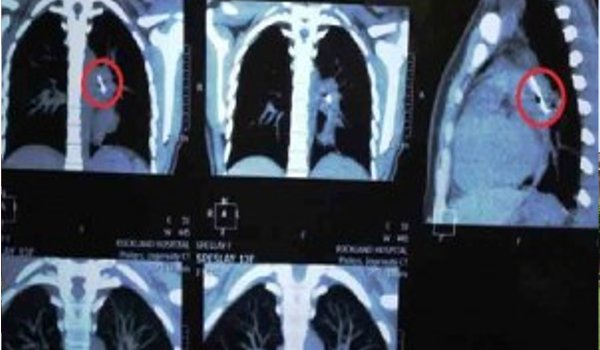

जिस पिन को उसने अनजाने में निगल लिया था, वह श्वसनी में घुस गया, जिससे गंभीर रूप से खांसी एवं बेचैनी होने लगी। एक्स-रे और सीटी स्कैन की शुरुआती तस्वीरों में पता चला कि यह पिन बाए द्वितीयक कैरीना में धंस गया था और बाई मुख्य फुफ्फुसीय धमनी में फंस गया।